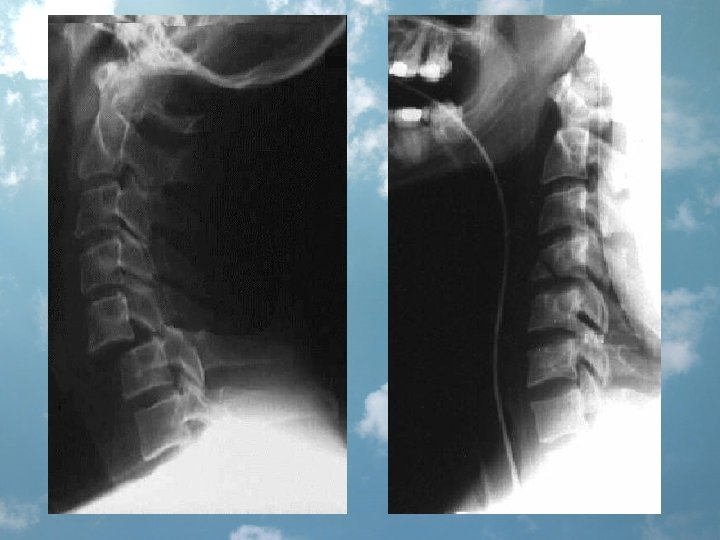

Assume the cervical spine to be unstable until proven otherwise • up to 50% of patients sustaining C-spine trauma develop neurologic abnormalities (nerve root compression and weakness to quadri- plegia and death). • 10% of patients with C-spine injury are initially neurologically intact, but develop deficits during the course of emergency care • risks of airway management

C-spine evaluation • bone and soft tissue • X-ray exam: „one view is no view”, L-all 7 C+Th 1 (30% inj. C 7 Th 1), AP-vertical alignment of the spinous and articular process and abnormalities in joint and disc spaces, open mouth view integrity of the atlanto-occipital and atlanto-axial joints, the odontoid process, oblique – intervert. foramina • CT • lateral cervical spine - sensitivity of about 85% 92% in a three view series 100% when selective CT scanning is employed